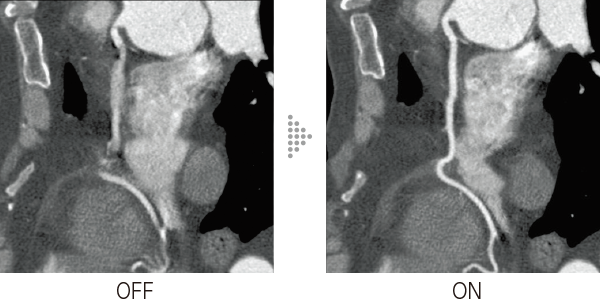

The motion correction technology that was previously applicable to cardiac CT examinations(ECG Scan) has been applied to body examinations without synchronization to meet further clinical demands.Body StillShot provides images with minimal motion blur by maintaining the continuity of the body axis direction over a wide range when calculating the direction and amount of movement of the subject in four dimensions from the collected RawData. The use of an algorithm that does not require ECG data makes it easier to apply to routine examinations. It can also be used in combination with Intelli IPV*2, an image reconstruction technology developed utilizing AI technology, contributing to even higher image quality.

- *2 IPV stands for Iterative Progressive reconstruction with Visual modeling. Intelli IPV was developed utilizing Machine Learning, an AI technology. The performance and accuracy of the system do not automatically change after use.